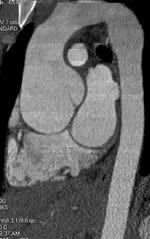

ABDOMINAL AORTIC ANEURYSM IMAGING SURGICAL AND PERCUTANEOUS ...

ABDOMINAL AORTIC ANEURYSM IMAGING SURGICAL AND PERCUTANEOUS SELECTION Abdul R. Halabi, MD, – Open surgery becomes standard of care for AAA . Albert Einstein . Parodi JC, Palmaz JC, Relative contra-indication to ... Fetch Content